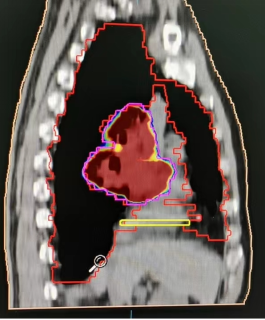

1、肺癌横断面及矢状面肿瘤处治疗剂量显示图

2、咽部肿瘤横断面及矢状面治疗剂量显示图

3、计划系统效果图:黄色线内-蓝色线外深颜色区域为高剂量区域,黄色线外及蓝色线内为低剂量区域。即照射剂量区域可按肿瘤治疗的需要进行调节。